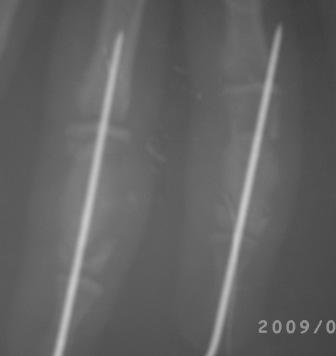

20.03.09г. операция. Экскохлеация не получилось, стенки диафиза фаланги как папиросная бумага, хотел сохранить хоть одну стенку, но и это не получилось - ломается и крошится, удалось сохранить оба эпифиза, проксимально чуть стенку и метафиза. В полости белесоватая кашицеобразная масса. Дефект заполнен сформированной под фалангу аутопластикой из гребня подвздошной кости, сверху ушита надкостницей, пальцевые сосуды сохранены. Материал отправлен на гистологию. Фикация спицей трансартикулярно, вынужденно фиксировали оба сустава - но это мне никак не нравится!

Р-снимки отправлю в понедельник.

Послеоперационные x-ray некачественные, всё ж кое что можно разглядеть, постараюсь повторно снять!

Абдурашид.